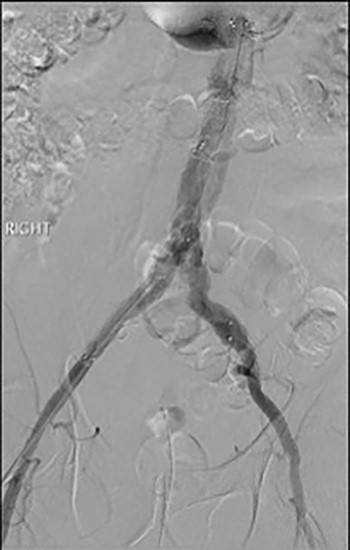

3D reconstruction CT scan, at 6-week interval from index procedure.

The patient was transferred to the high-dependency unit for observation during the thrombolysis. After 4-h, the patient was taken back to Interventional Radiology department for a check angiogram (Fig. 3). This demonstrated a fully re-canalized aorto-iliac system with no distal thrombotic or embolic complications. The thrombolysis infusion was stopped at this stage. In the post-operative period, anticoagulation has been continued with Apixaban. A CT scan 6 weeks post-procedure has confirmed ongoing patency of the endograft with no visible thrombus (Fig. 4).